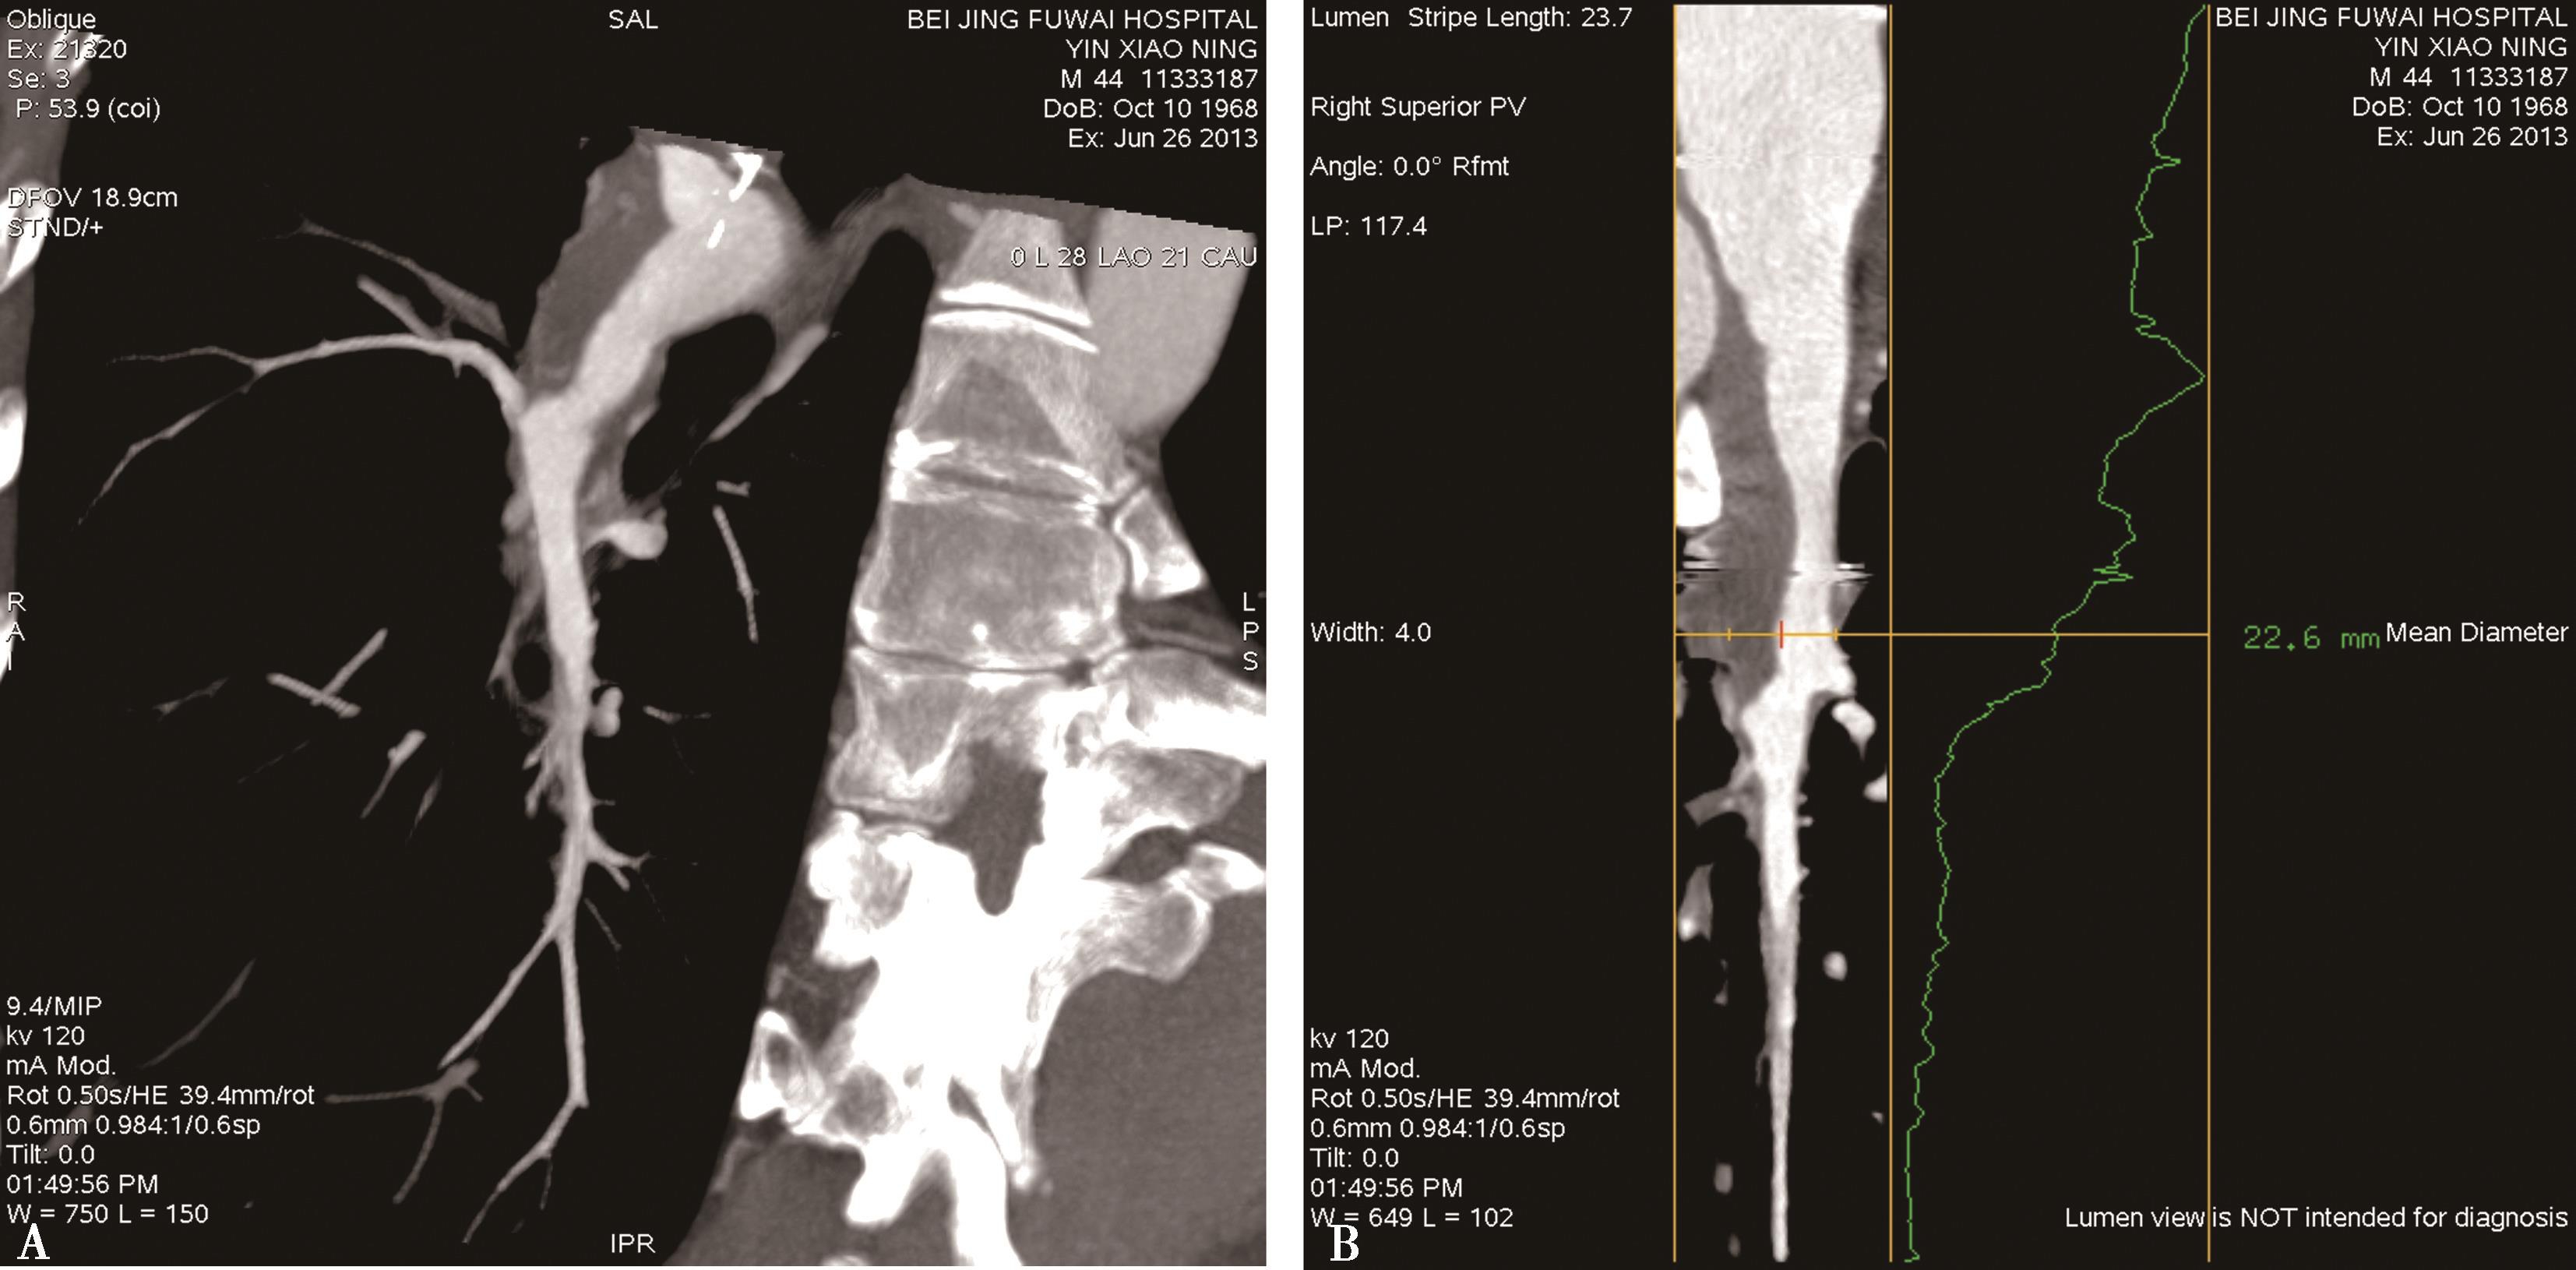

五、多排螺旋CT肺静脉造影方法

多排螺旋CT肺静脉造影检查多用于:①左心房-肺静脉检查,用以检查左心房,左心耳和肺静脉的解剖,评价肺静脉,评估左心房大小,检出左心房(耳部)血栓,指导临床诊断及射频消融治疗;②肺静脉疾患:肺静脉瘤,肺静脉狭窄,闭塞;回流异常等(包括先天性或获得性)。CT检查可以减少对有创检查的依赖、减少患者负担,有重大的优势。

(一)多排螺旋CT肺静脉造影检查方法

1.扫描的范围 从主动脉弓上水平到心脏膈面。

2.主要参数 以64排VCT为例,增强扫描参数设定为:电压120kV,电流400~600mA,机架转速0.35秒/圈,螺距为0.984∶1,准直器宽度为2.5mm,重建层厚0.625mm,视野(FOV)为25cm,矩阵512×512。由于采用的是智能监测跟踪技术。

3.扫描采用智能对比剂跟踪技术,监测层面设定在左心房的层面,ROI定为左心房,触发阈值定义为100~120HU。

4.对比剂 对比剂浓度320~370mgI/ml,采用单筒高压注射器团注,流率为4.0~5.0ml/s,对比剂总量为70~90ml。

5.一期扫描 当ROI的CT值达到阈值时启动增强扫描程序。第一期扫描得到完整的肺静脉-左心房图像。如果达到诊断目的,可结束扫描(图8-1-11)。

图8-1-11 肺静脉CTA检查

A.上肺静脉(↑);B.下肺静脉(↑);C.肺静脉最大密度投影。LSPV:左上肺静脉;LIPV:左下肺静脉;RSPV:右上肺静脉;RIPV:右下肺静脉